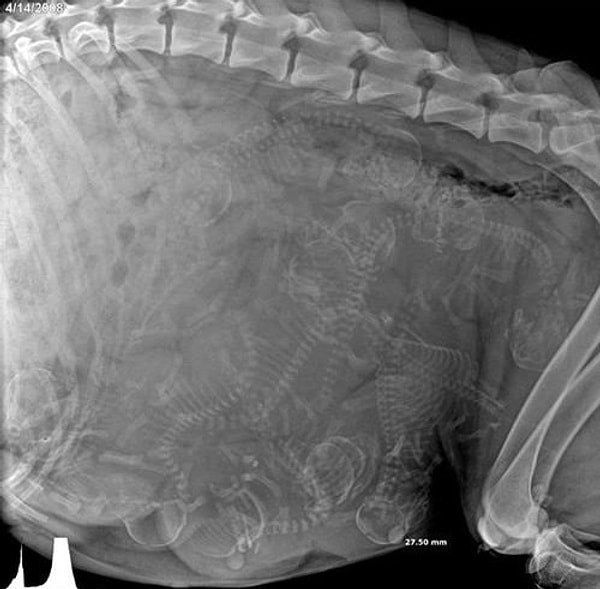

1. Змея